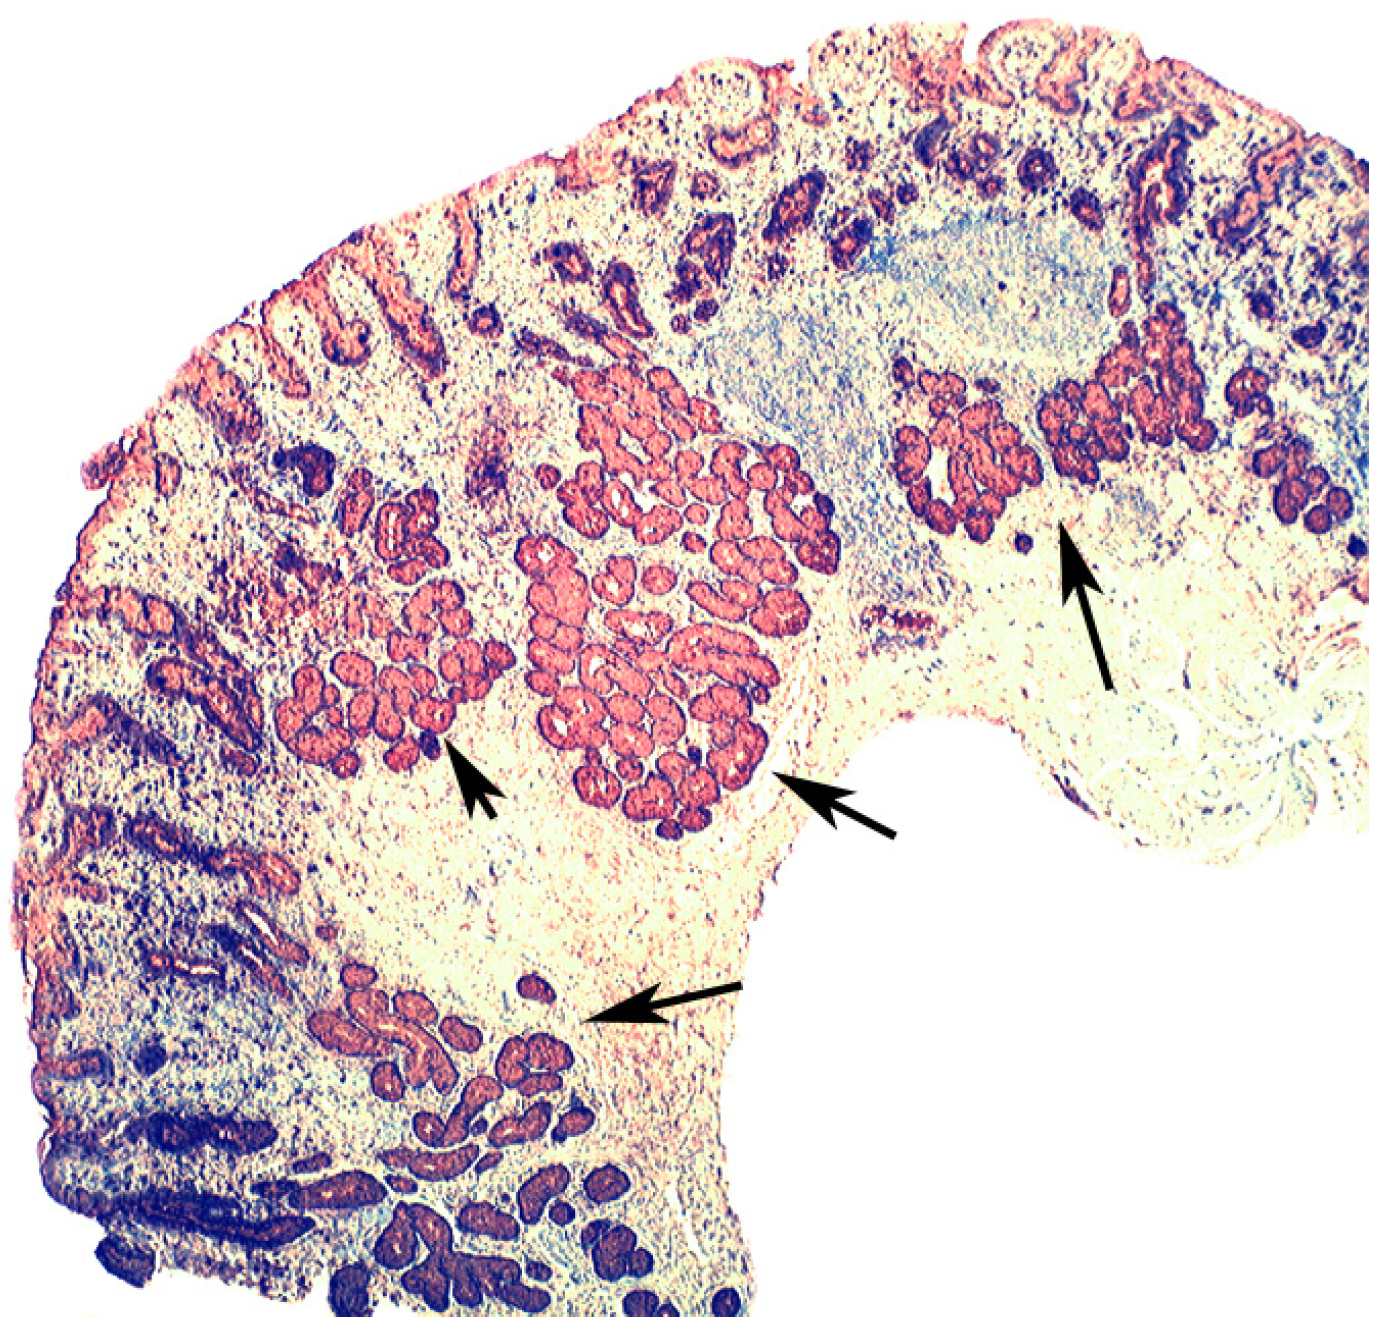

Figure 7.

Autoimmune gastritis (corpus) showing lysozyme expression in pseudopyloric glands at arrows (lysozyme immuno-stain, ×4).